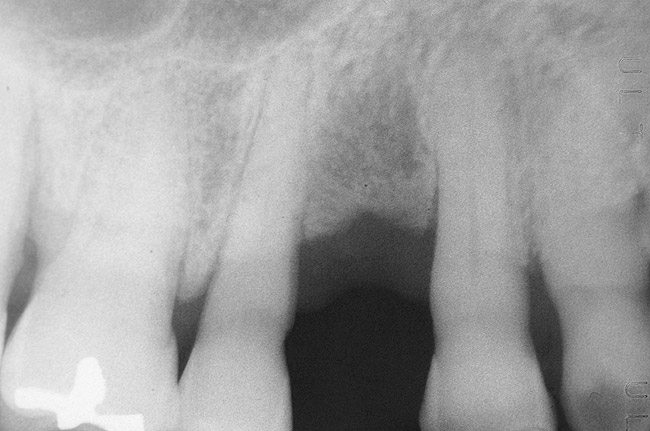

Figure 14  Radiographic view of the case seen in Figure 13 showing complete bone fill of the periodontal defect (the bone graft used was mostly radiolucent).

Figure 14